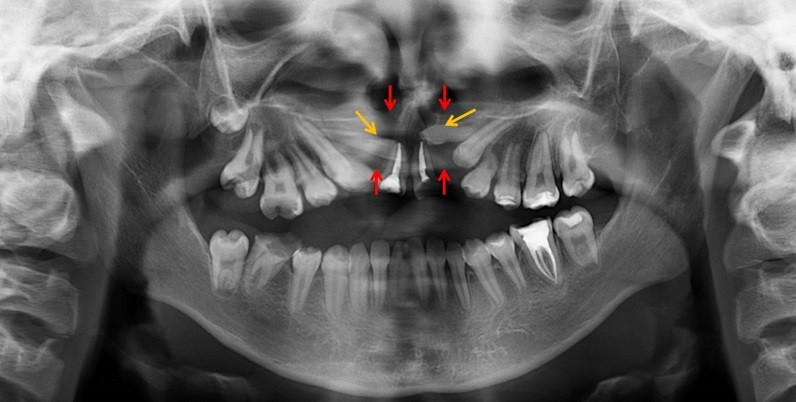

La tomografía de haz cónico, por medio de las vistas axiales, nos muestra la extensión en sentido mesiodistal de estos defectos, la misma que ocasiona la pérdida de las tablas óseas bucal y lingual, además del agujero y conducto nasopalatino (flechas rojas). Por otro lado, se aprecia la relación de las piezas supernumerarias con las raíces de las piezas vecinas (flechas amarillas) (Fig. 2).